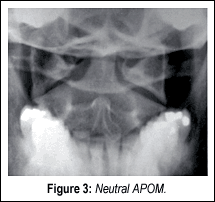

In the APOM, the odontoid should sit equidistant between the articular masses of the atlas. The lateral atlantoaxial (AA) joints are symmetrical in position and configuration. Normally, the principal motion of the AA articulation is rotation, although flexion, extension, lateral translation and vertical approximation also occur to some degree at this level.

Most of us will only see Type I in our offices. If there is asymmetry between the dens and the lateral masses on the APOM, lateral views in the APOM projection should be performed, especially if there is a history of trauma. Excessive lateral side slippage of C1 on C2 is indicative of rupture or laxity of the accessory ligaments (check ligaments). Cervicocranial axial rotation is primarily limited by the AL, supported by the tectorial membrane, the accessory AA ligaments and the joint capsules.